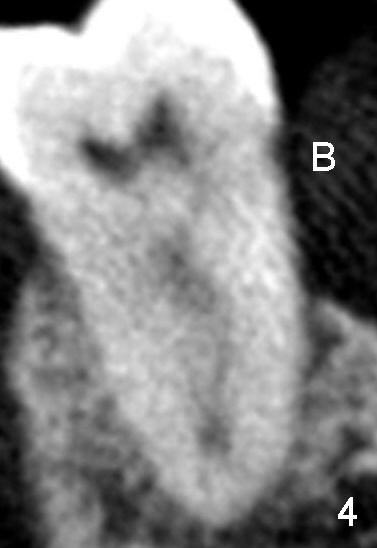

CT近中根断面显示它仍然有两个根管,但是它们非常接近(图四;B:颊侧),由于近中根弯曲(图一至图三),我们必须做多个CT切面(没有用图逐个显示)才能以上结论,不过让我们用图五示意图表明:箭头指向近中两个根管共同部分,两根红线代表这两个根管相对独立部分(它们两者之间有一个峡部(*),但是两者仍有沟通),然后它们在根尖处融合,最后由一个主要分支(蓝线)出去(术中十五号扩大针抵达根尖狭窄处;图五黄线代表小分支),总之,大部分感染牙髓组织被清洗(峡部也被磨掉或者搞通了),根管充填(图六黑色部分),所以术后疼痛消失,但是必须做牙冠防止冠部细菌进入,严密观察。